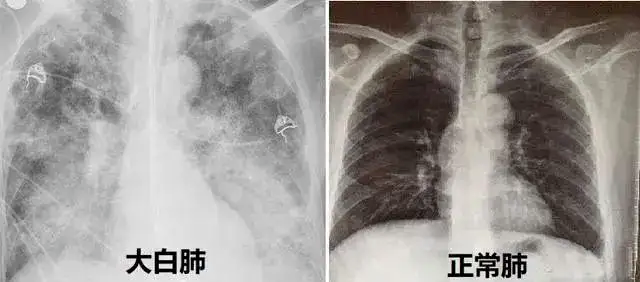

医院急诊科住院总医师何凯介绍,该患者入院时CT显示其双下肺有实变,氧饱和度只有50%左右,而正常人的氧饱和度在95%~99%。病人入院以后就被送进ICU!“病情进展很快,两天之后就进入一个‘白肺’状态,甚至出现呼吸衰竭。”据了解,氧饱和度过低就提示有严重缺氧,身体也可能因为缺氧而引起多脏器损伤,还可能会影响心肌的血供,导致呼吸的抑制,引起心肌损伤,呼吸骤停等严重后果,甚至威胁生命。

何医生介绍,病人入院以后就被送进ICU,“病情进展很快,两天之后就进入一个‘白肺’状态,甚至出现呼吸衰竭,虽然经过多日治疗,他的氧饱度已经能达90%左右。”